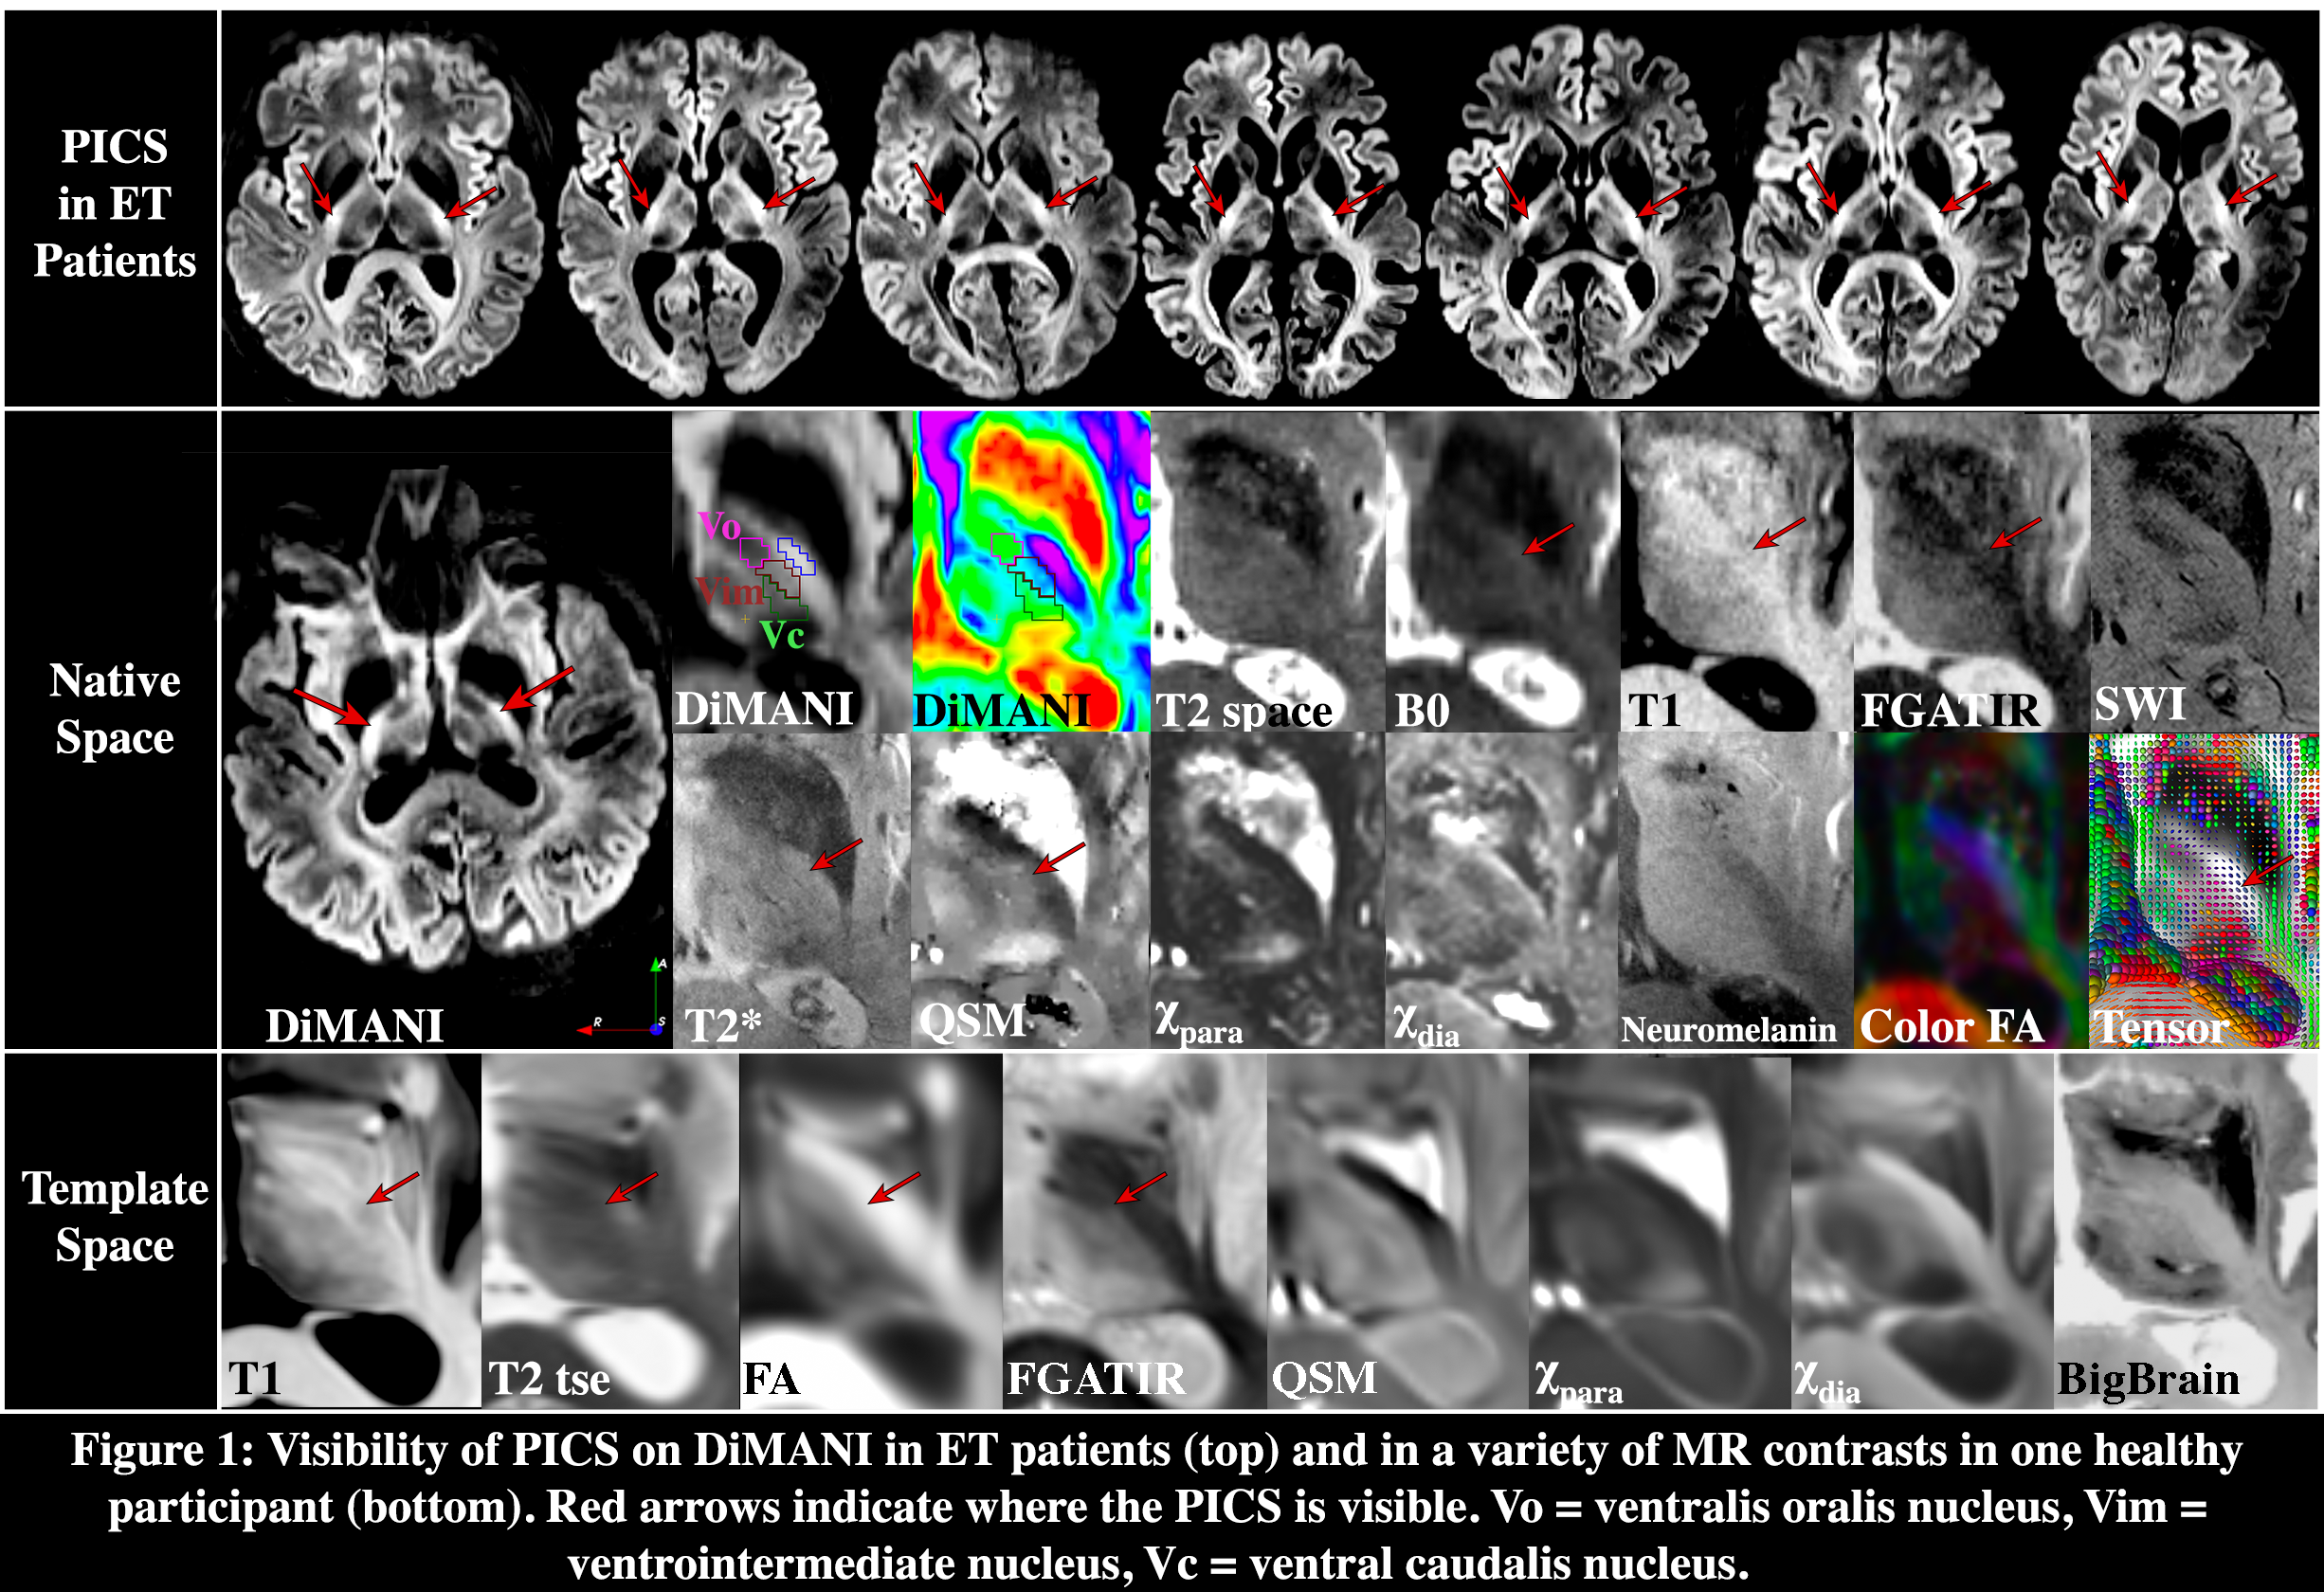

Results: PICS was consistently identified across multiple MRI sequences, but more easily idendified in DiMANI sequences in all patients (Fig.1). Tractography analyses identified PICS to correlate with the distribution of motor fibers from the internal capsule (Fig.2A-C). For the M1 homunculus, two somatotopic clusters were observed: one including mostly trunk, lower and upper limbs; and another, more anteriorly, with head/face clustering with tongue/larynx (Fig.2D-F). Intra-operative stimulation at two different depths resulted in pLIC-specific side effect in the tongue/face. At those depths, measurements showed closer proximity of the DBS electrode to M1 clusters of head/face and tongue/larynx, validating the imaging findings (Fig.3).

Fig.1